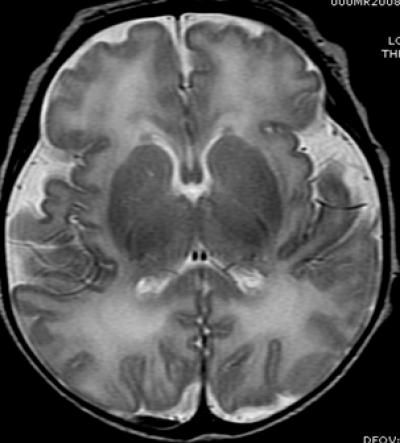

Dr. Blüml and colleagues have been studying preterm infants to learn more about how premature birth might cause changes in brain structure that may be associated with clinical problems observed later in life. Much of the focus has been on the brain's white matter, which transmits signals and enables communication between different parts of the brain. While some white matter damage is readily apparent on structural magnetic resonance imaging (MRI), Dr. Blüml's group has been using magnetic resonance spectroscopy (MRS) to look at differences on a microscopic level.

In this study, the researchers compared the concentrations of certain chemicals associated with mature white matter and gray matter in 51 full-term and 30 preterm infants. The study group had normal structural MRI findings, but MRS results showed significant differences in the biochemical maturation of white matter between the term and preterm infants, suggesting a disruption in the timing and synchronization of white and gray matter maturation. Gray matter is the part of the brain that processes and sends out signals.